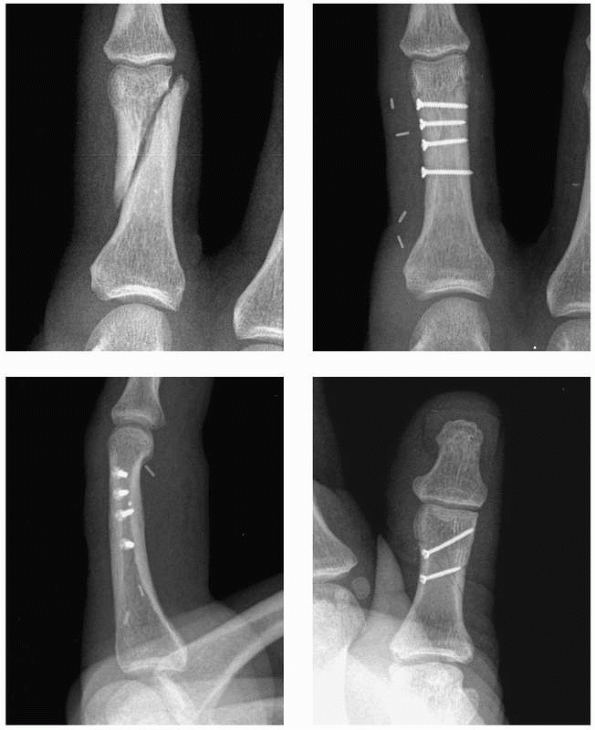

internal fixation (Fig. 28-2). In a study

FIGURE 28-2

Major open hand trauma frequently requires the most stable forms of fixation to facilitate an aggressive early motion rehabilitation program focusing on tendon gliding. |